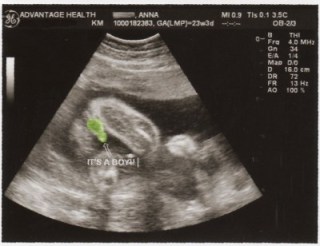

At my hospital ultrasound during my first pregnancy, I tried really hard to see if I could tell the sex. Girl parts look like a hamburger, and boy parts look like a turtle. See?

Boy = turtle!